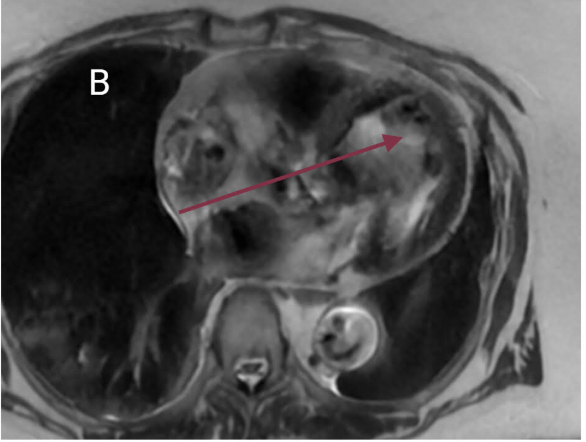

A 76-year-old woman with a significant smoking history presented with dizziness. Evaluation for syncope revealed normal orthostatic vitals and electrolytes. Electrocardiogram showed sinus bradycardia (heart rate 48 bpm) without QTc prolongation. Non-contrast CT of the head and CT angiography of the head and neck were unremarkable. Chest X-ray demonstrated left upper lobe atelectasis. Contrast-enhanced CT of the chest revealed bronchial obstruction in the left upper lobe and multiple pulmonary nodules in the right lung. Bronchoscopy identified a fungating mass obstructing the left upper lobe bronchus; biopsy confirmed adenocarcinoma. Transthoracic echocardiogram showed preserved left ventricular ejection fraction (60–65%), concentric hypertrophy, and grade I diastolic dysfunction. Cardiac MRI revealed a 3 cm mass along the basal anterior wall of the left ventricle with heterogeneous T2 signal intensity, consistent with myocardial metastasis. With a diagnosis of adenocarcinoma, the patient was advised to follow up as an outpatient for further oncologic management and advanced cardiac imaging.

This case highlights an incidental myocardial metastasis from lung adenocarcinoma in a patient presenting with bradycardia and dizziness, symptoms that may be related to cardiac involvement. While pericardial metastases are more common, myocardial infiltration is rare and often asymptomatic. Cardiac spread may occur via hematogenous, lymphatic, or transvenous routes and can present with arrhythmias, effusions, or hemodynamic compromise. Echocardiography is useful for initial evaluation, but cardiac MRI provides superior detail in assessing lesion characteristics and differentiating tumor from thrombus. Multimodal imaging plays a key role in identifying occult cardiac metastases that may impact clinical management.